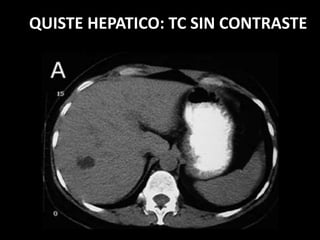

PROCESO CONGENITO: QUISTE

HEPÁTICO

• Quiste simple

• Circular

• Membrana periférica

• Contenido econegativo.

• Refuerzo posterior.

US QUISTE HEPATICO

QUISTE HEPATICO: TC SIN CONTRASTE

QUISTE HEPATICO: TC CON CONTRASTE